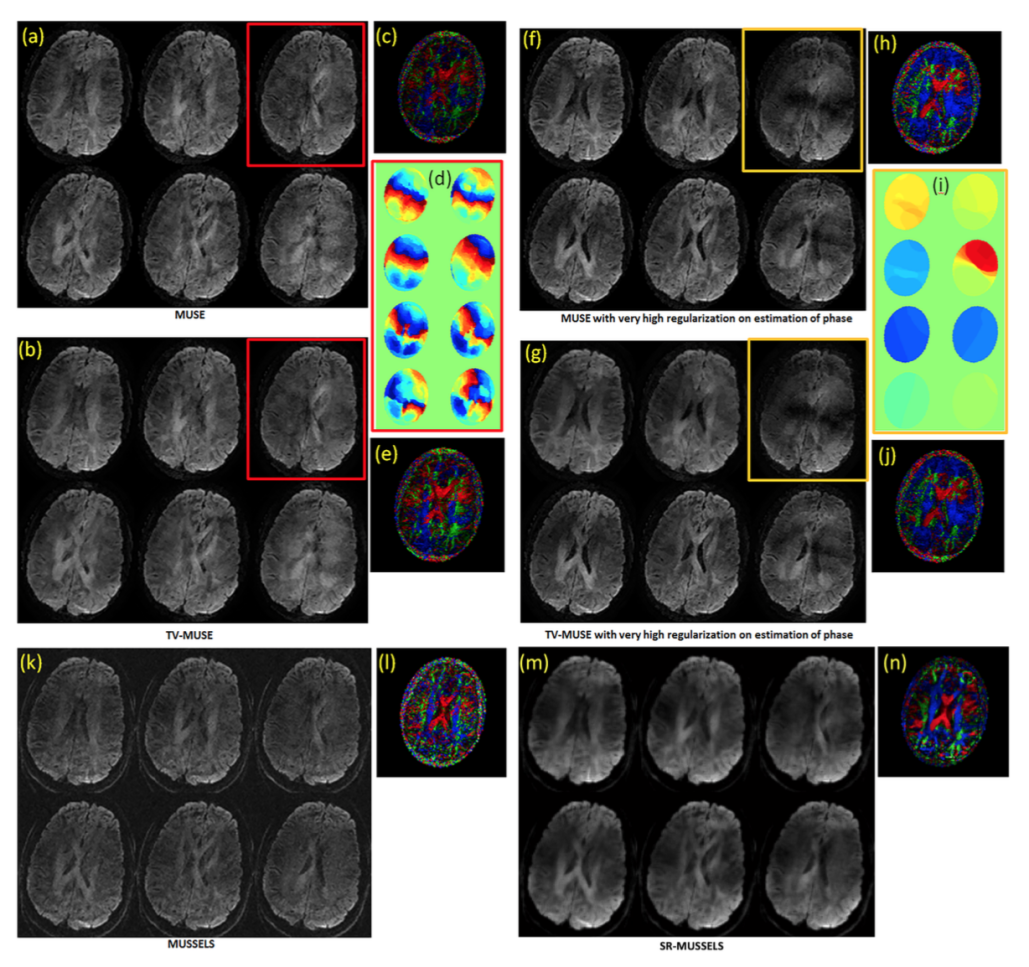

Regularized reconstruction for under-sampled multi-shot DWI

The previous experiments demonstrate the utility of MUSSELS to recover the fully sampled MS-DWI data. Here we show here that the regularized version of MUSSELS can be used to recover under-sampled MS-DWI data as well. For this purpose the 4-shot MS-DWI data was first under-sampled uniformly by skipping every other k-space lines from each of the shots. The top two rows of figure 8 shows the reconstruction of the 4-shot under-sampled MS-DWI data using TV-MUSE and SR-MUSSELS. This experiment highlight the situation where phase-based methods will fail. The inadequate unalising is evident in all DWIs reconstructed by MUSE. The regularized MUSSELS has performed reasonably well with significantly fewer artifacts seen visually in the reconstructed images. The color-coded FA maps generated from the six DWIs highlights the errors in the individual reconstructions. Interestingly, if the under-sampling pattern is changed slightly, the performance of both the methods improve significantly. The bottom rows of figure 8 shows the results of reconstruction where a non-uniform under-sampling pattern was employed. Specifically, the center k-space lines of each of the shots were kept intact. The improvement in the reconstruction results can be appreciated from the DWIs as well as the color coded FA maps. This behavior is not surprising and adds evidence to the fact that reconstructions from a slightly non-uniform under-sampling patterns provides more reliable results than a strictly uniform under-sampling pattern while using sparsity/low-rank -based reconstructions (33).

Fig 8: 4 shot under-sampled MS-DW data. (a) shows the TV-MUSE and SR-MUSSELS reconstruction of 3 DWIs reconstructed from uniformly under-sampled data. The under-sampling pattern is shown on the right side. (b) shows the unregularized as well as regularized MUSE and MUSSELS reconstruction of 3 DWIs reconstructed from non-uniformly under-sampled data. The under-sampling pattern used is included which shows that the center-k-space lines were kept intact for all the shots. The unregularized reconstructions also performed reasonably well with the non uniform under-sampling pattern.

Figure 8: 4 shot under-sampled MS-DW data. (a) shows the TV-MUSE and SR-MUSSELS reconstruction of 3 DWIs reconstructed from uniformly under-sampled data. The under-sampling pattern is shown on the right side. (b) shows the unregularized as well as regularized MUSE and MUSSELS reconstruction of 3 DWIs reconstructed from non-uniformly under-sampled data. The under-sampling pattern used is included which shows that the center-k-space lines were kept intact for all the shots. The unregularized reconstructions also performed reasonably well with the non uniform under-sampling pattern.